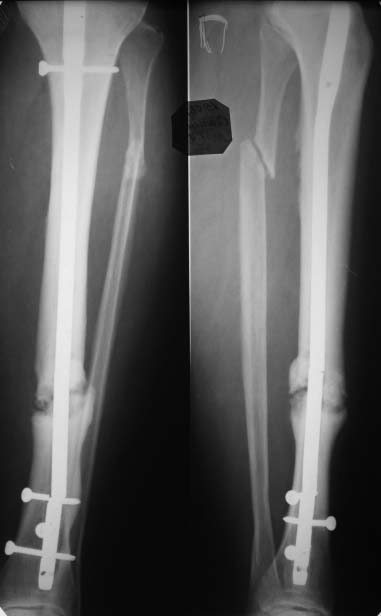

Большое спасибо за советы! Сегодня прооперировал больную. Все дистальные винты были сломаны, но они легко удалились, сломанные концы просто выбивал на противоположную сторону (использовал для этого обломок старого сверла 3,2)и через проколы вынимал.Попытался удалить гвоздь целиком с помощью спицы с оливой, но она не пропустила запирающую спицу до дистального обломка стержня. Помучился. Пришлось удалять по частям,проксимальный экстрактором,открыл зону ложного сустава, вынул промежуточный фрагмент иглодержателем, а вот дистальный обломок стержня уже получилось удалить с помощью спицы с оливой, но заклинивал её кистевой спицей. Ещё раз большое спасибо всем за участие!